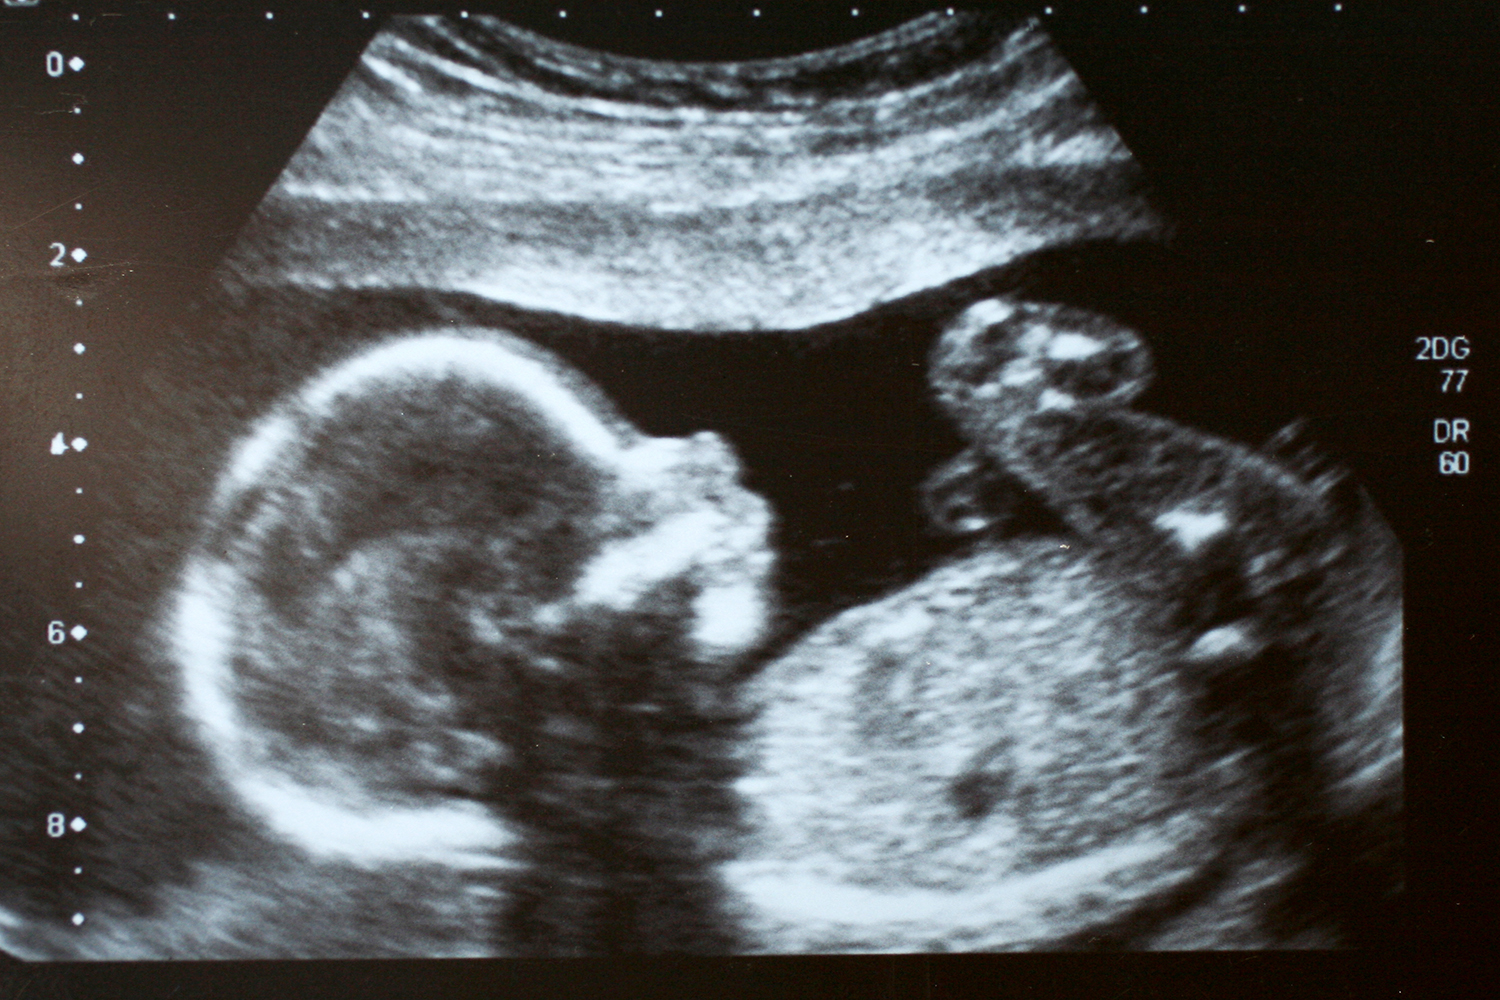

The incidence of ATM is unknown because most fetuses with the disorder die before delivery. The condition occurs when both parents are carriers for thalassemia. In places where women have access to prenatal care, ATM is usually suspected on ultrasound and confirmed by DNA analysis in the second trimester.